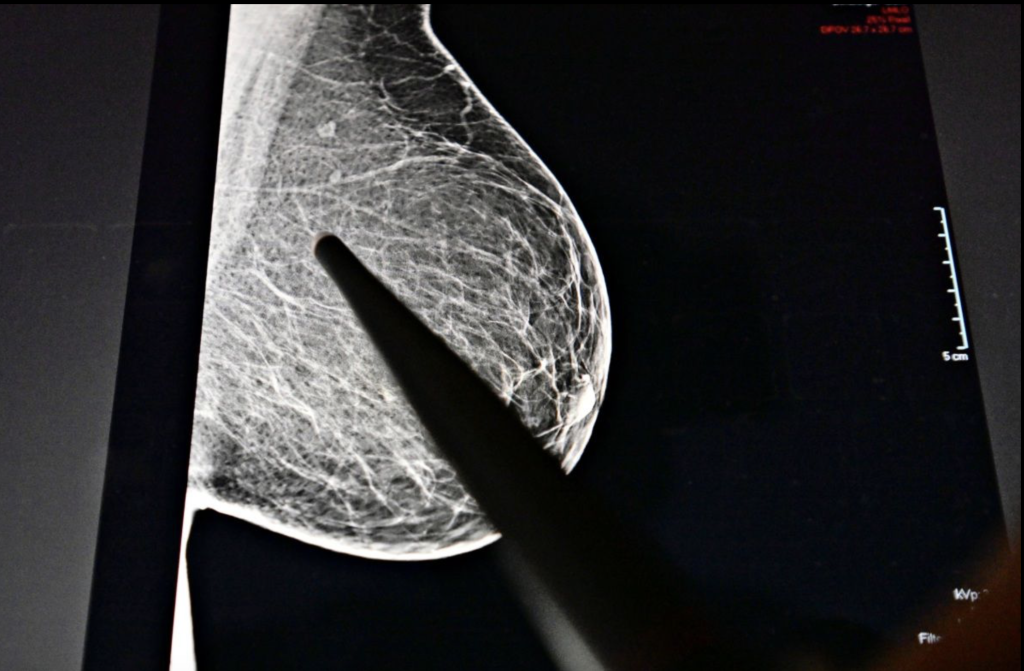

Großes Problem sei die Früherkennung. Besser gesagt, die nicht vorhandene Früherkennung. Denn routinemäßige Mammografie-Screeningprogramme werden Frauen ab 45 Jahren empfohlen, jüngere sind üblicherweise nicht die Zielgruppe für Früherkennungsmaßnahmen.

Dass hier raschest möglich ein Umdenken stattfinden muss, zeigt auch eine neue US-Studie, die am Montag auf der Jahrestagung der Radiological Society of North America (RSNA) vorgestellt wurde. Ziel der Studie war es herauszufinden, wie häufig Brustkrebs unter jungen Frauen auftritt, in welchem Stadium sich die Tumoren befinden und wie sie entdeckt wurden. Dafür analysierte das Team die Daten von sieben ambulanten Einrichtungen im Umkreis von New York. Mit dem Ergebnis: Zwischen 2014 und 2024 wurden insgesamt knapp 1800 Brustkrebsfälle bei Frauen im Alter von 18 bis 49 Jahren diagnostiziert. Das waren jährlich zwischen 20 und 24 Prozent aller Brustkrebsfälle – also fast ein Viertel aller Brustkrebspatientinnen sind bereits unter 49 Jahre alt. "Diese Studie zeigt, dass ein erheblicher Anteil der Krebserkrankungen bei Frauen unter 40 diagnostiziert wird, einer Gruppe, für die es derzeit keine Vorsorgerichtlinien gibt", erklärt dazu die Radiologin Stamatia Destounis.

Besonders alarmierend: In 80,7 Prozent der Fälle wurde ein invasiver Tumor diagnostiziert, viele waren aggressiv

Und: Wie anhand der Studie ebenfalls festgestellt wurde, liegt das Durchschnittsalter bei der Diagnose bei 42,6 Jahren. Besonders alarmierend auch hier: In 80,7 Prozent der Fälle wurde ein invasiver Tumor diagnostiziert. "Die meisten dieser Krebserkrankungen waren invasiv, das heißt, sie konnten sich über die Brust hinaus ausbreiten, und viele waren aggressiv – insbesondere bei Frauen unter 40", sagt Destounis. "Einige waren triple-negativ, eine Form von Brustkrebs, die schwieriger zu behandeln ist, da sie nicht auf gängige hormonbasierte Therapien anspricht."